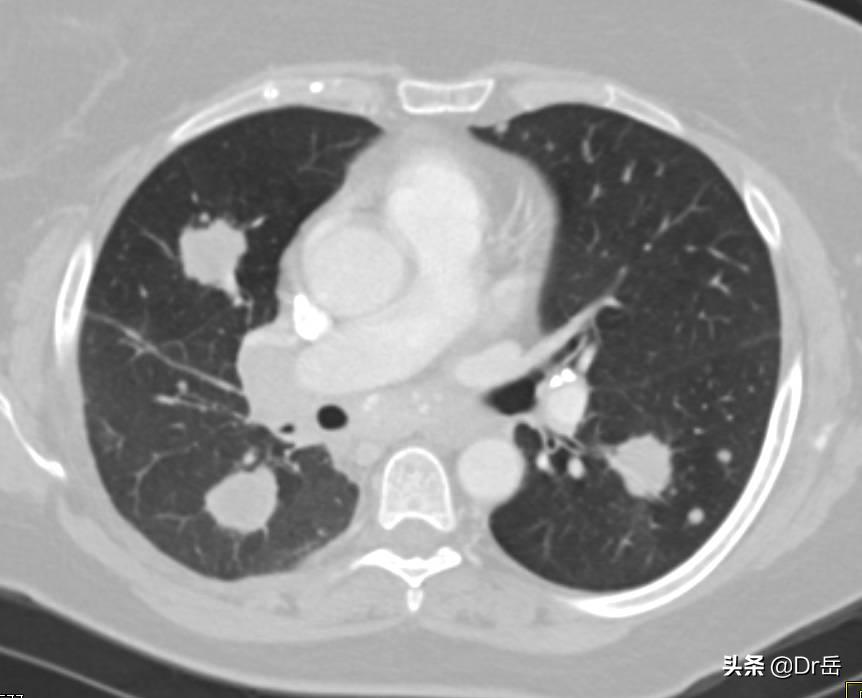

CT:肾癌肺转移

比较可靠的研究表明,转移性肾癌做手术是对患者有益的,能够改善患者的生存质量,有可能能够提高生存期。手术切除的目标主要有两个,一个是原发灶,也就是将患癌的肾切除;二是对肾癌转移灶的切除,比如肾癌的肺转移,但是转移灶的切除只限于孤立性的转移,如果是多发转移,手术就没有太大的意义了。

- 如果患者是孤立性转移灶,而且对免疫、靶向治疗反应差的情况下,可以进行转移灶的切除。转移灶切除的同时也是要对原发灶进行切除的。